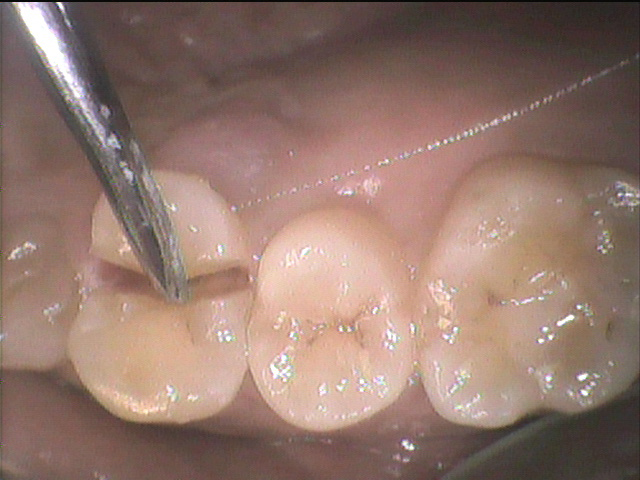

②銀歯を被せた歯がまた虫歯を再発する

銀歯と歯は歯科用の接着材でペタンとくっつけています。

しかし、正確にいうとぴったりとくっついているわけではありません。

封鎖性が非常に弱いため隙間があるのです。

銀歯を入れる際に歯との隙間を接着材で埋め、

くっつけているだけ、です。

隙間があるので隙間からは細菌は侵入し放題です。

お口の中には目に見えない何百億の細菌が存在します。

侵入し放題の虫歯菌により、せっかく治療した歯の中に虫歯が再発します。

銀歯のセメントも劣化してくるので、古い銀歯の中で、元々の歯が真っ黒になっていたといったこともよくあります。